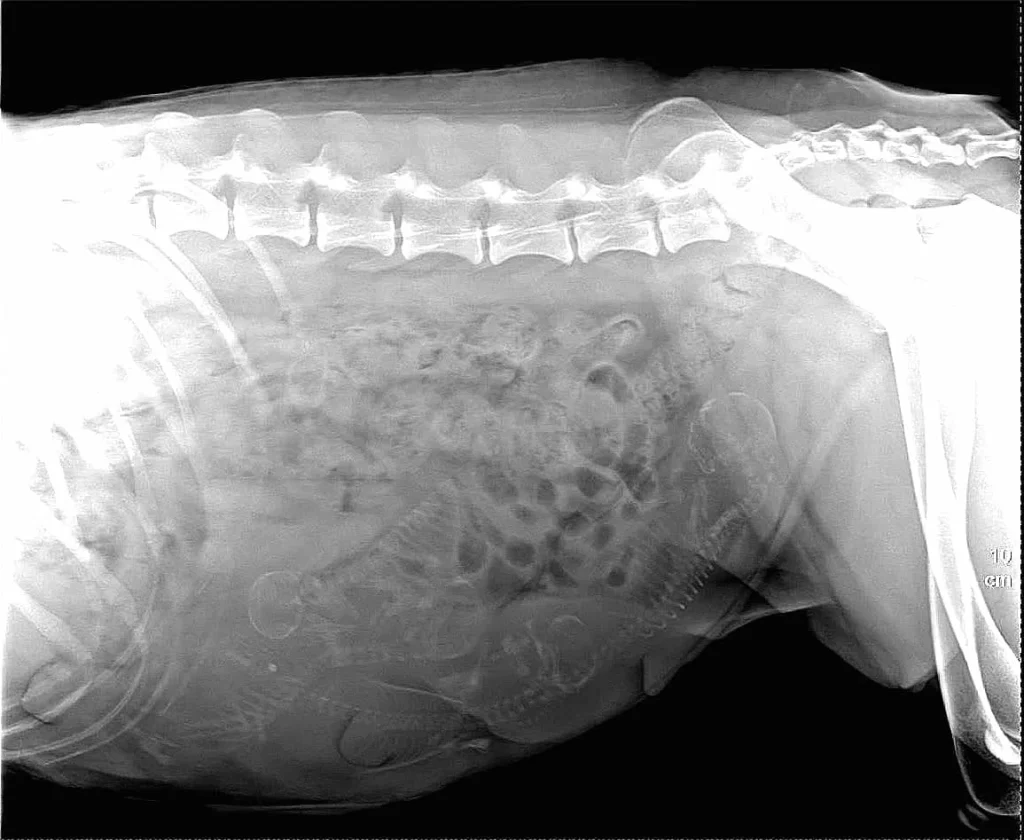

Rentgenska slika breje psice; izveden je bil carski rez.